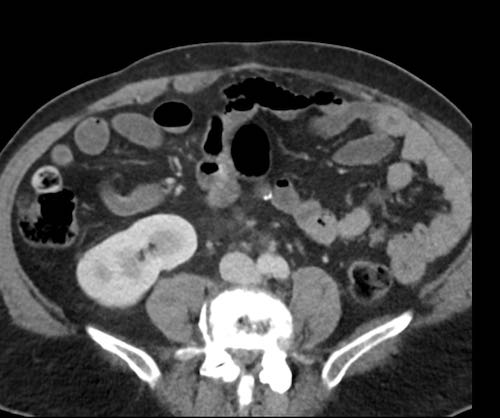

Ca lâm sàng 2

Cuộn qua các lát cắt.

Bạn có thể phát hiện tất cả các tổn thương cấy ghép phúc mạc không?

.jpeg)